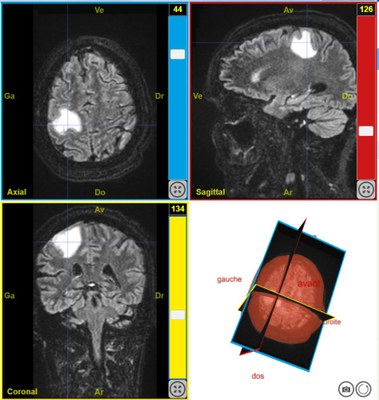

IRMsujet12222PathologieTumeurAudition T2Flair

Par Sandrine Beaudin